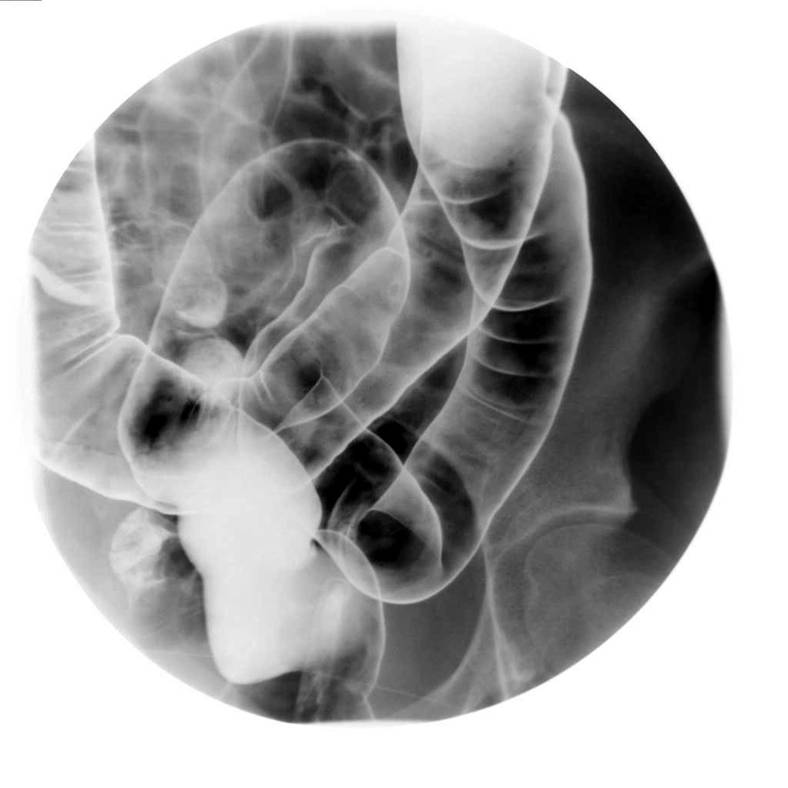

大腸攝影檢查

| 主要檢查大腸有無解剖異常、通過障礙、潰瘍、腫瘤、憩室、息肉等所有大腸內或外之病灶。病患若有血便、慢性腹痛、腹瀉或排便習慣改變、體重減輕等徵兆,皆可藉此檢查作更進一步的治療評估。 | ||||||||||||